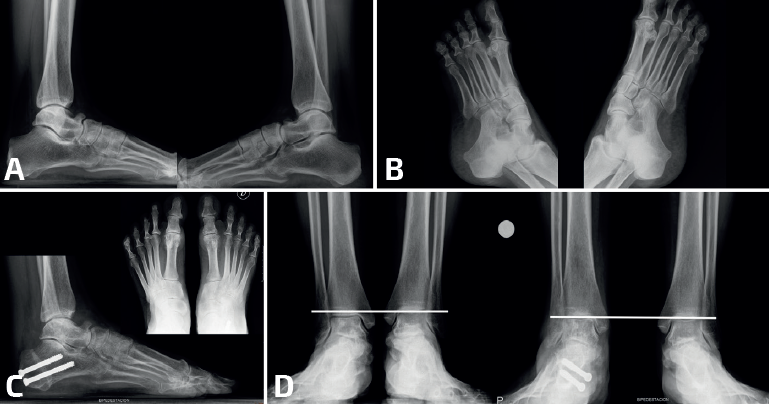

La mayoría de las coaliciones atípicas se diagnostican como hallazgos casuales al solicitar radiografías simples en pacientes con dolores en los pies, generalmente con deformidad en plano valgo. Las proyecciones convencionales –dorsoplantar y lateral– de ambos pies en carga suelen poner ya de manifiesto coaliciones atípicas como las talonaviculares y las calcaneocuboideas. Las proyecciones oblicuas son importantes porque suelen mostrar algunas coaliciones como las naviculocuboideas, las cuneometatarsianas y las coaliciones tarsales masivas. Las radiografías de ambos tobillos en carga suelen mostrar la consecuencia de algunas coaliciones tarsales masivas en forma de tobillo en cúpula (ball-and-socket)(13). Se han descrito varios signos radiológicos asociados a las coaliciones atípicas, como el “signo de la seta” en las talonaviculares, aunque algunas coaliciones atípicas presenten signos ya conocidos en las típicas, como el talar beak en las calcaneocuboideas o el del “oso hormiguero” en las naviculocuboideas(14)(Figura 1).

- Talonavicular: la mayoría de las coaliciones talonaviculares son congénitas, con herencia autosómica dominante, pero en algunos casos pueden formarse durante la preadolescencia(16). En el estudio radiológico es característico el “signo de la seta”, visible en las radiografías en carga en proyección dorsoplantar, donde los contornos de la fusión ósea remedan la forma de un hongo(14)(Figura 2). Es frecuente la existencia de este tipo de coalición en síndromes malformativos como el de Nievergelt-Pearlman(17). Cuando una coalición talonavicular es sintomática, suele serlo de manera leve, con molestia más que dolor(18,19,20,21,22). En la mayoría de los casos el tratamiento conservador suele ser suficiente para mejorar la sintomatología(23,24). Cuando es necesaria una cirugía, suele realizarse una corrección de la deformidad con una osteotomía(25).

- Calcaneocuboidea: las coaliciones calcaneocuboideas suelen encontrarse en combinación con otras coaliciones (Frost y Pensieri) y también en el contexto de cuadros sindrómicos como el de Crouzon(26,27,28). Revisando nuestra casuística de coaliciones, los autores encontraron un caso de una paciente no sindrómica con una coalición aislada calcaneocuboidea bilateral que cursó con un pie plano valgo muy sintomático. La cirugía, consistente en una osteotomía varizante de calcáneo, mejoró la deformidad en valgo y la clínica hasta conseguir que la paciente estuviera asintomática (Figura 3).

- Múltiples/Masivas: las coaliciones tarsales múltiples/masivas (dos o más de dos en el mismo pie) pueden presentarse como casos aislados no sindrómicos o asociados a otros problemas dentro de un síndrome (Figura 4). Se han descrito casos no sindrómicos de coaliciones combinadas calcaneonavicular, talonavicular y talocalcánea, con frecuencia bilaterales(26,50), y también afectando a la articulación tarsometatarsal(51). La mayoría son asintomáticas y algunas cursan con inestabilidad y entorsis de repetición en el paciente adolescente(50). En algunos casos observamos que la clínica depende del desarrollo de reacciones de estrés en los huesos limítrofes, como en el caso de un paciente con coaliciones tarsales talocalcáneas y naviculocuboideas y con dolor en la cuña intermedia(52). Aunque la mayoría mejoran con tratamiento conservador, existen casos publicados con cirugía de resección con mejoría de los síntomas(50,53,54,55,56,57). En muchas coaliciones múltiples/masivas del tarso, el tobillo (tibiotalar) tiene que adaptarse para poder trabajar como una tibiotalar y una subtalar a la vez, lo que conlleva un crecimiento adaptado a la función, formándose un tobillo cóncavo-convexo (ball and socket en la literatura anglosajona)(58)(Figura 5). En la mayoría de los casos, el hallazgo es casual y el paciente está asintomático. En línea con otras coaliciones, en los pacientes sintomáticos la clínica deriva de un pie plano-valgo. Las soluciones mecánicas consisten en el uso de plantillas con un buen gradiente supinador o en una cirugía de realineación mediante una osteotomía supramaleolar de cierre con base medial(59,60). En algunos pacientes con artrosis subtalar o tibiotalar avanzadas, los procedimientos de realineación pueden combinarse con artrodesis(61,62).

- Corrección de la alineación, sin actuar sobre la coalición: en coaliciones óseas con deformidad (habitualmente en plano valgo). La osteotomía más habitual es la varizante de calcáneo, en coaliciones óseas talonaviculares, calcaneocuboideas y múltiples/masivas. Este tratamiento es el más frecuente en nuestra experiencia (Figura 6). Pero si existe un abducto del pie, una osteotomía de alargamiento de la columna lateral con una osteotomía de tipo Evans puede corregir la deformidad y mejorar el dolor. La supinación residual del antepié en coaliciones múltiples/masivas puede precisar de una plantarización del primer radio con una osteotomía de tipo Cotton. En pies con coaliciones tarsales masivas que originen tobillos cóncavo-convexo, las osteotomías supramealeolares permiten mejorar la valguización del retropié y la sintomatología dolorosa. El cambio de paradigma del tratamiento mediante cirugías de realineación sin actuar sobre la coalición ha derivado del tratamiento de las coaliciones talocalcáneas. De hecho, recientemente hemos formulado y publicado una nueva clasificación de coaliciones talocalcáneas con unas indicaciones de tratamiento que son extensibles a la mayoría de las coaliciones atípicas con una desaxación(64).